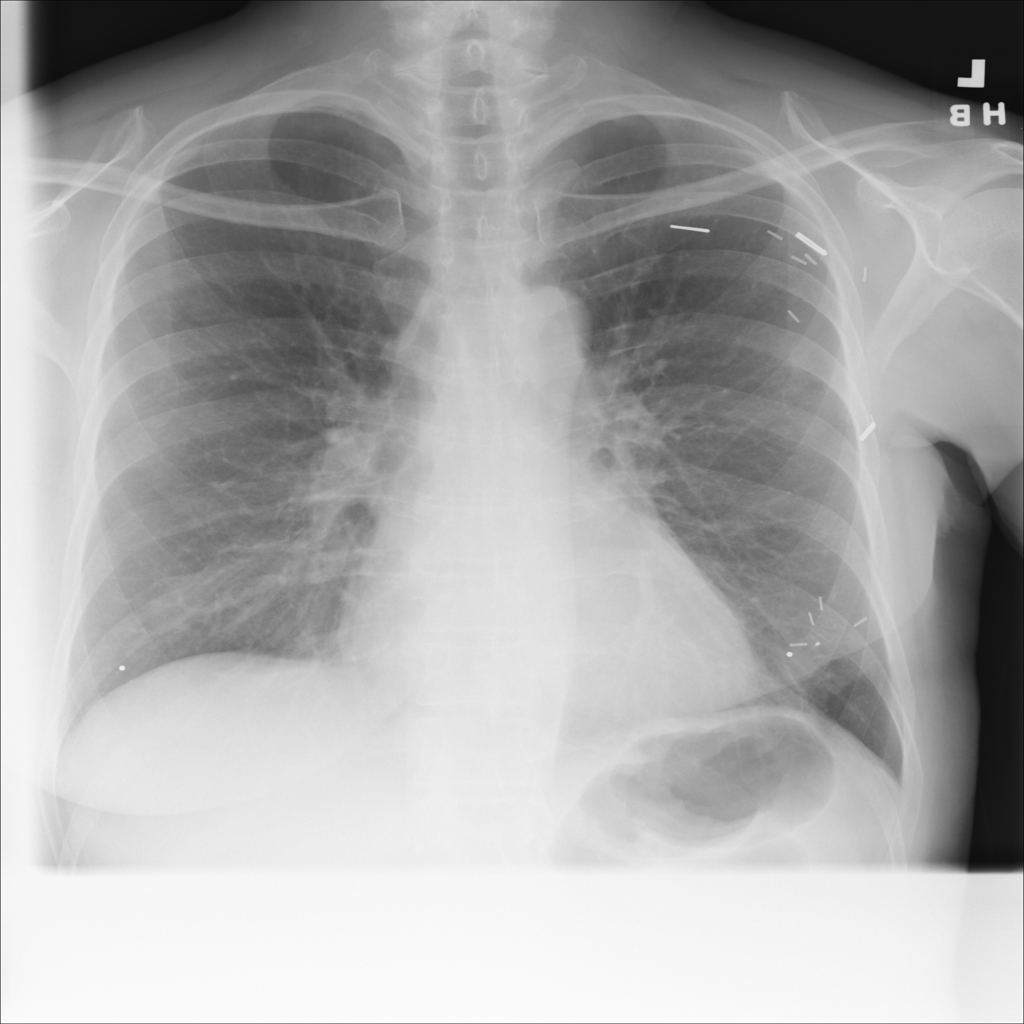

Showing up to 90 reference images for Nodule.

PAT-50E5 · IMG-000Nodule

PAT-50E5 · IMG-000

PA